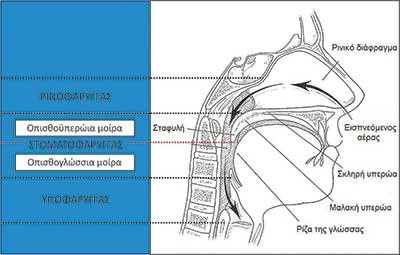

Εικόνα 1

Η αιτιολογία του ΣΑΑΥ είναι πολυπαραγοντική. Στον φαρυγγικό αυλό των πασχόντων παρατηρούνται στενώσεις (Εικόνα 1) λόγω τοπικής εναπόθεσης λίπους (παχυσαρκία), πάχυνσης των πλάγιων φαρυγγικών τοιχωµάτων, αύξησης του µεγέθους της γλώσσας και της µαλακής υπερώας, οιδήµατος των βλεννογόνων (κάπνισµα, ροχαλητό) και δυσµενούς κρανιοπροσωπικής ανατοµίας (οπισθογναθισµός και µικρογναθία). Πέρα, όµως, από τη στατική θεώρηση της ανατοµίας του φαρυγγικού αυλού, εξίσου σηµαντική, αν όχι σηµαντικότερη, είναι η δυναµική συµπεριφορά των ευένδοτων φαρυγγικών τοιχωµάτων κατά τη διάρκεια του ύπνου, η οποία σχετίζεται µε πολύπλοκους νευροµυϊκούς µηχανισµούς. Το σύνδροµο προσβάλλει παχύσαρκα άτοµα, καθώς και άτοµα φυσιολογικού σωµατικού βάρους, τα οποία έχουν δυσµενή σκελετική κρανιοπροσωπική διάπλαση. Ευνόητο είναι ότι άτοµα στα οποία συνδυάζεται παχυσαρκία µε δυσµενή σκελετική ανάπτυξη του προσώπου πάσχουν από το σύνδροµο µε ιδαίτερα µεγάλη βαρύτητα. Το ΣΑΑΥ παρουσιάζεται και σε παιδιά, κυρίως λόγω υπερτροφικών αδενοειδών εκβλαστήσεων και φαρυγγικών αµυγδαλών. Τέλος, ΣΑΑΥ µπορεί να διαγνωστεί στη συντριπτική πλειονότητα περιπτώσεων κρανιοπροσωπικών συνδρόµων (Pierre-Robin, Apert, Crouzon, Pfeiffer, Treacher-Collins) λόγω εξαιρετικά δυσµενούς κρανιοπροσωπικής ανατοµίας.